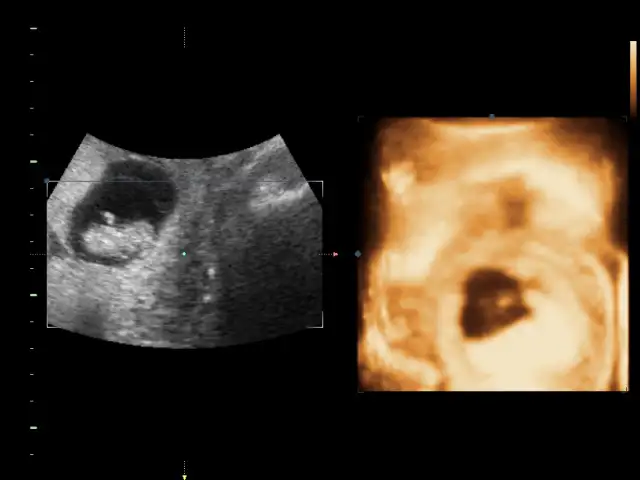

sağol canım ağzına sağlıkCanım seninkini erkek bebeğe benzettim ikinci Fotoğrafın alt kısmında bir şeyler var gibi. Ama bebek arkasını dönmüş bu teori için yandan ya da önden olması lazım Fotoğrafın.

Canım nub teorisi için 12-13 haftalar en ideal haftalar. Kese teorisine koy istersen ama bence o teori nub teorisi gibi bilimsel değil.

ben nub göremedim. yani anlamadım fotodan

Bu bebek durusu degisik geldi goremedim bisey canim

Bacakları açık aslında hiç çıkıntı yok gibiBu bebek durusu degisik geldi goremedim bisey canim